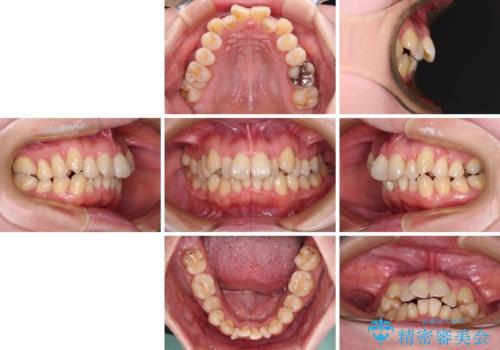

飛び出した上顎前歯と上下のデコボコ 片顎の抜歯によるワイヤー矯正

- 上下前歯のデコボコと、上顎の八重歯を気にして来院された患者様です。

下顎に対して上顎が前方にあり、第一大臼歯による咬合状態は上顎前突であったため、上顎のみ左右の第一小臼歯を抜歯し、ワイヤー装置にて矯正治療を行うこととしました。